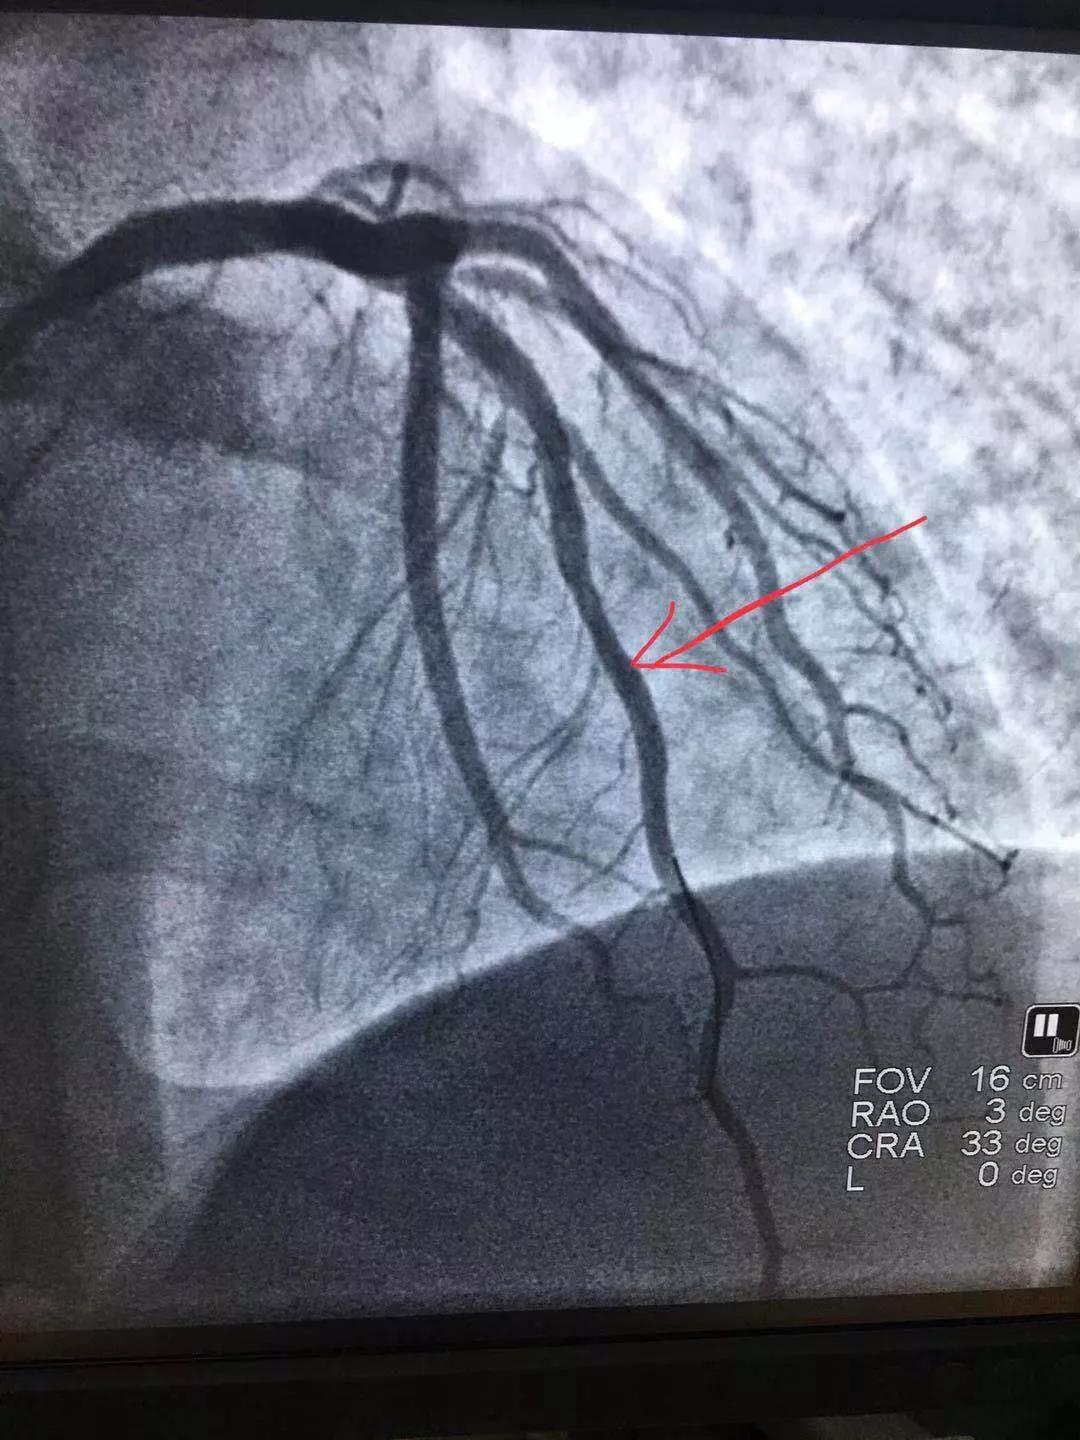

手術(shù)前與手術(shù)后情況

術(shù)中倫主任、徐遵敬副主任發(fā)現(xiàn)病人心臟前降支冠狀動(dòng)脈完全閉塞,征求病人同意后馬上植入支架治療。當(dāng)冠狀動(dòng)脈開通的一煞那,病人胸痛馬上消失,并在手術(shù)臺(tái)上發(fā)出了“我不痛了,我舒服了,你們真是再世華佗”的感嘆。術(shù)后病人曾出現(xiàn)頻發(fā)室性早搏,一過性左束支傳導(dǎo)阻滯,經(jīng)嚴(yán)密治療后病情好轉(zhuǎn)穩(wěn)定。